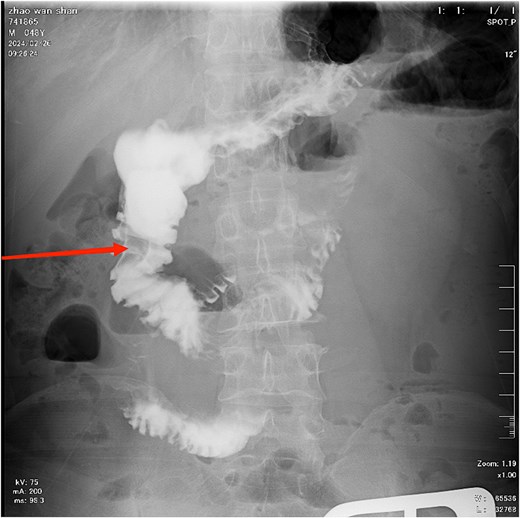

Diagnosis on admission: (i) Acute intestinal obstruction; (ii) Electrolyte disorders (low sodium, low chloride, and low calcium); (iii) Diabetes mellitus; (iv) Gallbladder stones. After admission, water and fasting were immediately given, gastrointestinal decompression, enema, and maintenance of water and electrolyte balance. Further improvement of gastroscopy and colonoscopy showed no obvious abnormalities, and the patient's symptoms improved after conservative treatment. A total of 8 days after admission, the patient experienced worsening epigastric distension and pain. A gastrointestinal contrast study revealed an obstructive lesion located at the terminal ileum (Fig. 2). On the 9th day after admission, an exploratory laparotomy was performed. During the operation, a mixed-type stone measuring ⁓5×5 cm was found ⁓20 cm from the ileocecal valve. A small intestine incision was made to remove the stone, and the specimen was sent to the pathology laboratory for component analysis. Postoperatively, gastrointestinal decompression was continued, and the patient was kept nil by mouth for 6–8 days. The patient was advised to consume a small amount of warm saline, which was tolerated well without discomfort. Subsequently, the patient was allowed to consume a small amount of liquid diet, which was also tolerated without issues. Gastrointestinal decompression and fasting were then discontinued. On the 10th postoperative day, the patient had a bowel movement, indicating that the obstruction had been resolved, and no stenosis was observed at the ileal anastomosis site. The pathology laboratory reported that the submitted specimen consisted of a mixture of cellulose, hemicellulose, and tannic acid. Inquiry of medical history: the patient had previously had discomfort such as upper abdominal distension and pain, occasional nausea and loss of appetite, etc., which were not paid attention to and treated. According to the postoperative pathological component detection combined with clinical manifestations and the patient 's medical history, it can be considered that the terminal ileum stones are derived from gastric stones (Figs 3 and 4).

The black arrow indicates the gastric bezoar, and the white arrow marks the site of stone extraction.